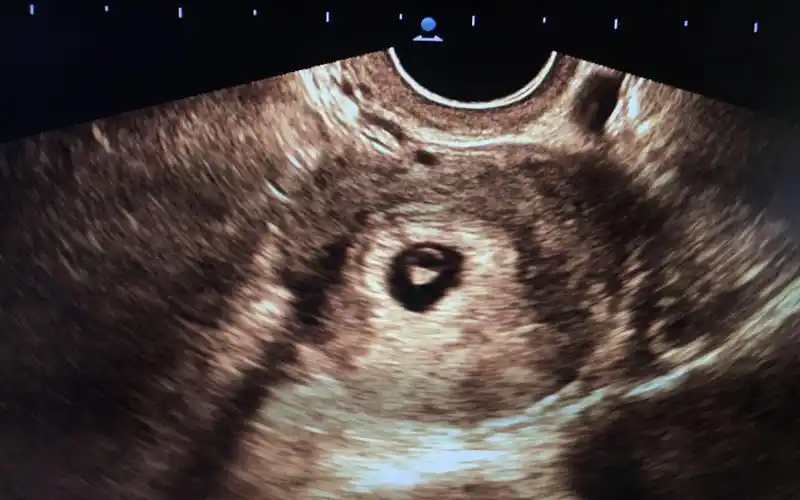

已生男孩孕囊图片分享根据数据和形状看男女真的很准

1长孕囊和圆孕囊的区别大不大

孕囊圆的是女孩吗

帮看孕囊这是长的,还是圆的

听朋友说的,孕早期的孕囊形状,长形的是男孩,圆形的_妈妈网孕育社区

孕囊形状为圆形就代表一定是生女孩吗